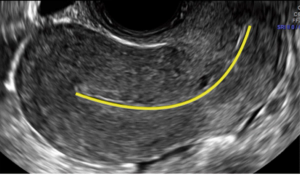

Flowchart: IUD insertionBySigrid Tristan, MD, MSc,Amna Dermish, MD, MScJuly 29th 2019This flowchart can help ensure a smooth procedure by helping the ob/gyn recognize potential challenges.